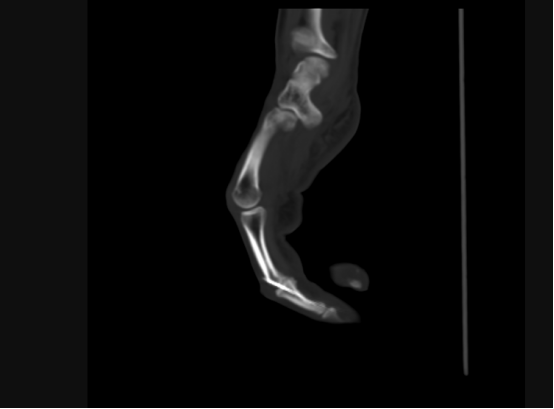

手术CT图

“所谓自体关节移植,就是将患者自身的关节进行移植和替换,相比传统的人工关节置换,该技术具有修复及时、没有排异反应、治愈效果明显等优点。”主刀医生胡明兴介绍,经放射医学科行三维CT精准动静脉及骨重建,在麻醉科的大力支持下,通过将脚趾关节及附近血管、神经、肌肉进行移植,他们仅用一次手术就为患者完成了手指修复,不需要多次开刀,尽可能保障了患者安全。